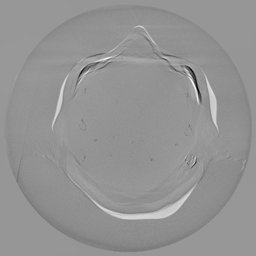

The results for simulated noisy data are shown in Fig. 2. The first and third rows display two representative slices from the test set, and the second and fourth rows present the corresponding error maps. The traditional WCE method suppresses cupping artifacts and recovers some missing anatomical structures but still shows noticeable deviations from the ground truth. Predictions from the four diffusion-based models demonstrate a markedly improved ability to restore anatomical structures. Among them, cDDPM fails to fully reconstruct the patient bed and retains residual noise in its outputs. This noise is attributable to an incomplete reverse denoising process rather than residual Poisson noise, as evidenced in our noise-free experiments (Fig. 5 in the Appendix). PatchDiffusion, diffusionGAN, and I2SB achieve similar visual quality, with I2SB producing the cleanest and most consistent reconstructions.

Quantitative results in Tab. V further confirm I2SB’s superiority over conventional deep learning methods such as FBPConvNet and Pix2pixGAN across RMSE, PSNR, and SSIM. Compared to other diffusion models—including cDDPM, PatchDiffusion, and cLDM—I2SB delivers higher image quality, while diffusionGAN achieves comparable quantitative performance. However, I2SB demonstrates a significant advantage in inference efficiency, as summarized in Tab. IV.